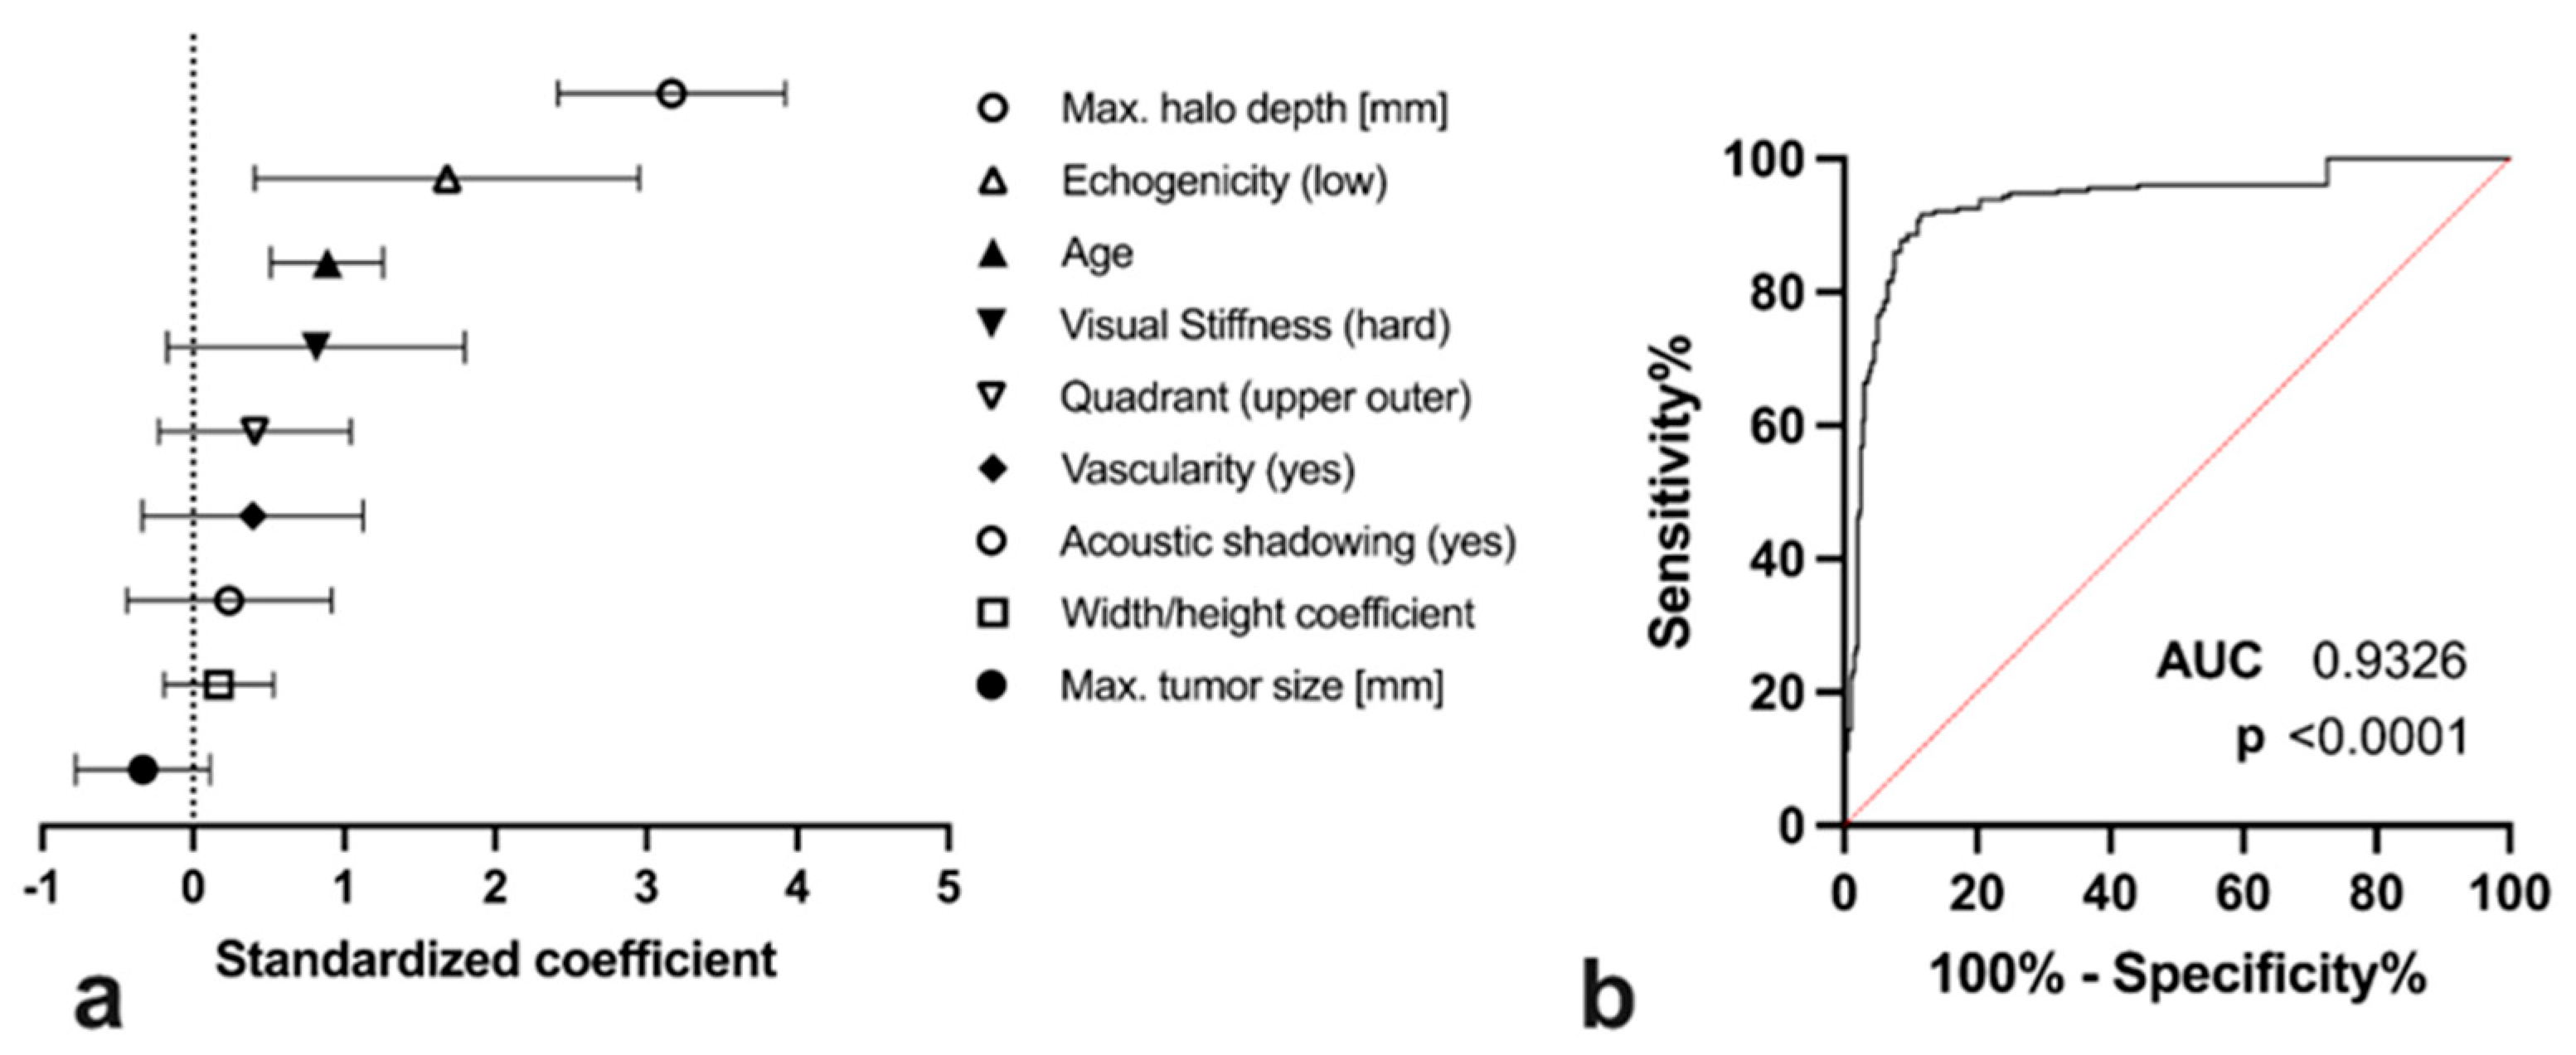

3.2. Covariates for Maximum Elastographic Peritumoural Halo Depth

3.3. Diagnostic Utility of SEPHmax Assessment

3.4. Comparison of SEPHmax to Other Demographic and Sonographic Tumour Properties

| SEPHmax | 0.6 ± 1.4 mm | 0.9 ± 1.4 mm | 5.5 ± 3.9 mm | >0.9999/<0.0001/<0.0001 |

| Tumour grade | Grade I | Grade 2 | Grade 3 | p-values $ |

| SEPHmax | 4.0 ± 3.9 mm | 5.6 ± 3.6 mm | 6.8 ± 4.2 mm | 0.001/0.0001/0.4291 |